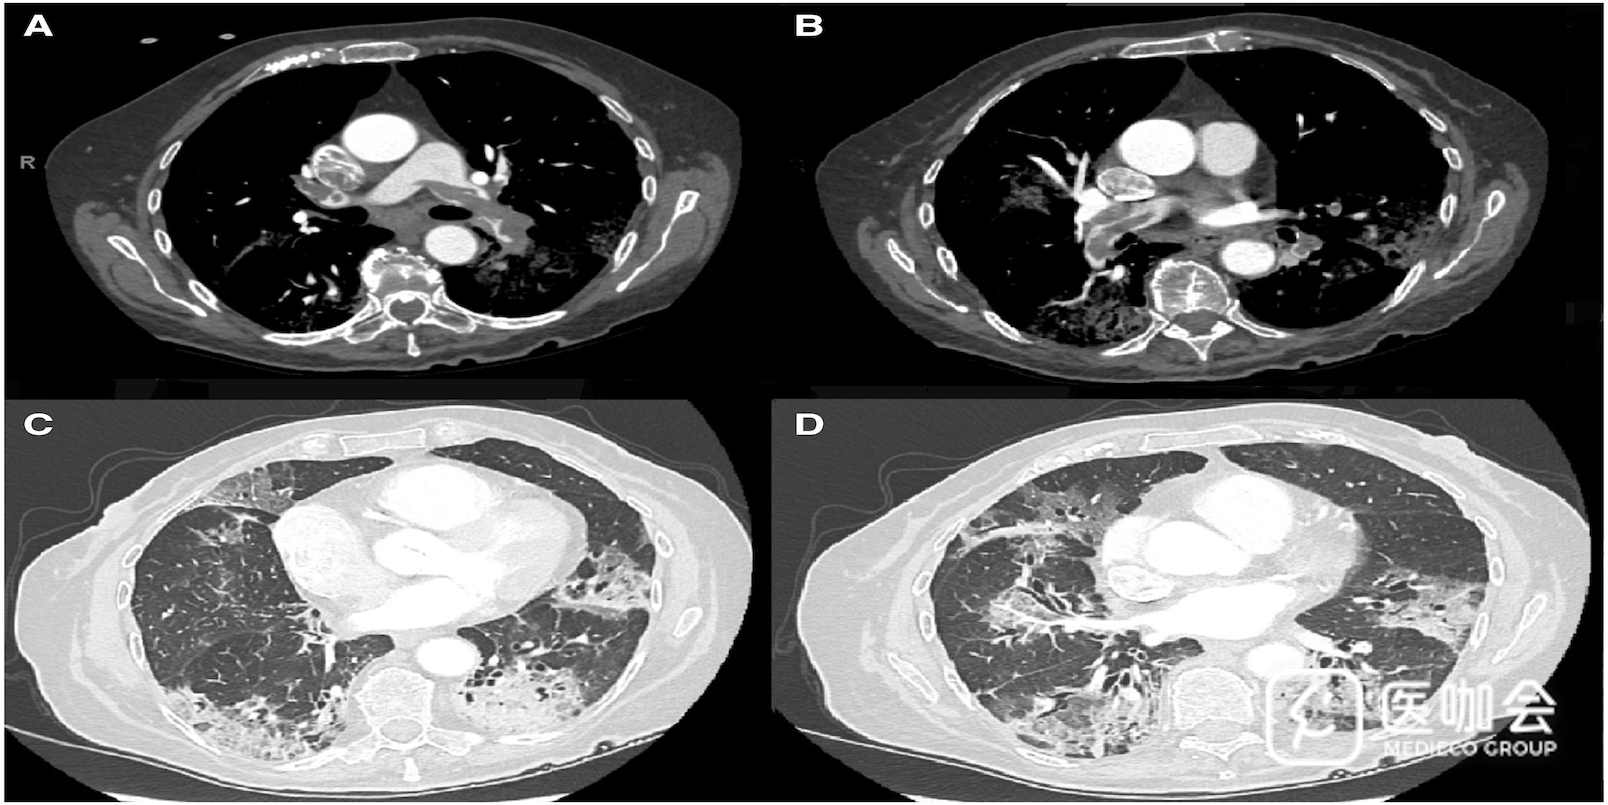

CT扫描发现双侧充盈缺损,诊断为肺栓塞(图1A和B),与累及双侧肺实质的广泛磨玻璃影有关,左肺下叶后基底段最为突出(图1C和D)。下肢加压超声检查呈阴性。